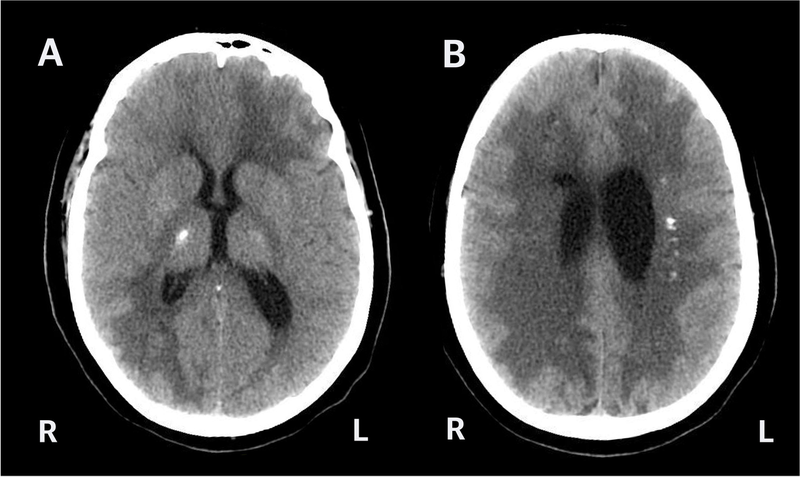

Phần lớn các trường hợp phát hiện khối nang ở não khi bệnh nhân bị chấn thương đầu, đau đầu hoặc được chỉ định phương pháp chụp CT não. Có thể nhiều người chưa biết, khối nang não vốn đã có sẵn trong đầu từ lúc chúng ta còn là sơ sinh và chúng phát triển theo tỷ lệ kích thước của sọ.

Chỉ số vách ngăn trong suốt não dưới 8mm thường được hiểu là kích thước ngã 3 não thất bên, trong đó nếu chỉ số này lớn hơn 10m là giãn não thất, trường hợp 8mm vẫn nằm trong giới hạn cho phép và nếu không có bất thường kèm theo thì không có vấn đề gì cả.